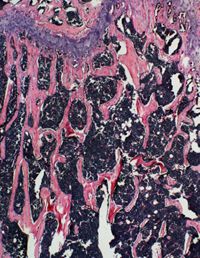

Wang’s team previously found that Wnt4 protein could promote bone formation; in the new study, they created a strain of transgenic mice in which the Wnt4 gene was overexpressed in osteoblasts, or bone-forming cells. As expected, those mice exhibited increased bone mass compared with the control group, and they showed significantly less bone loss in an osteoporosis model. Surprisingly, the team discovered that Wnt4 protein not only promotes osteoblasts, but also suppresses the activity of osteoclasts, or bone-resorbing cells, as well as inflammation in the bone marrow.

In order to understand the mechanisms of the action of Wnt4 protein, the researchers investigated its effect on NF-κB signaling — a key part of the process during osteoclast formation and bone inflammation. Mice with hyperactive NF-κB signaling developed arthritis-like symptoms and showed bone loss, but cross-mating these mice with Wnt4 transgenic mice effectively alleviated these symptoms. Wnt4 transgenic mice also displayed a slower decline of bone mass associated with advanced age. The team went on to show that Wnt4 protein could inhibit osteoclast formation in vitro by removing a protein important for NF-κB activation.